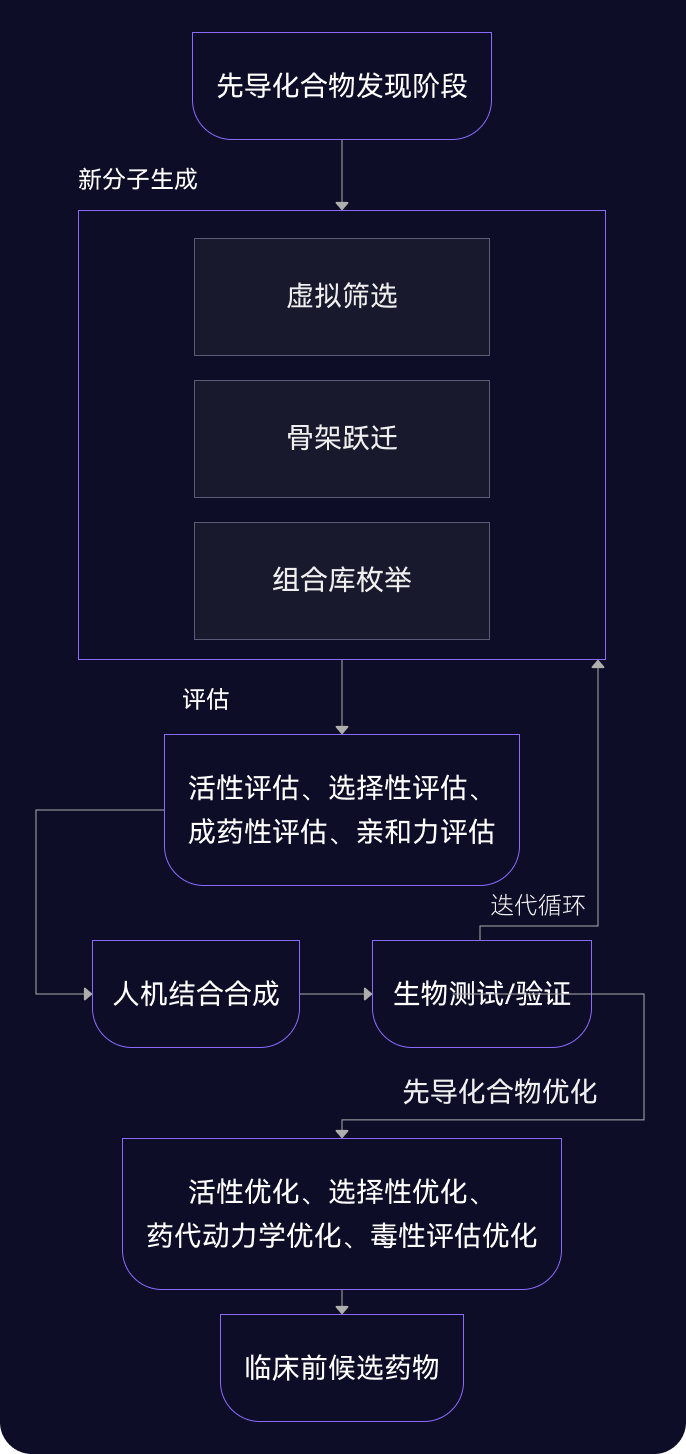

05 先導化合物階段

尋找最佳先導化合物

并優化成藥性質

先導化合物評估與優化

通過優化活性、選擇性和類藥性,將苗頭化合物轉化為先導化合物

- 利用生成式AI(XMolGen)進行分子和庫設計,增加骨架新穎性和化合物多樣性

- 通過先進的物理計算(XFEP)進行虛擬篩選,優化活性和類藥性

- 通過專有自動化平臺,實現快速且可靠的中間體和庫合成

自動化助力先導化合物優化

在進入臨床前試驗前,優化先導化合物提高療效和安全性,改善藥代動力學特性。

- 借助自動化濕實驗室化學能力,快速而穩健進行SAR分析,指導化合物設計

- 內部動物實驗室支持體內研究,包括藥代動力學/藥效學(PK/PD)、療效、安全性、劑量和代謝,推進臨床前開發

- 先進的力場技術,準確計算自由能微擾,預測結合親和力